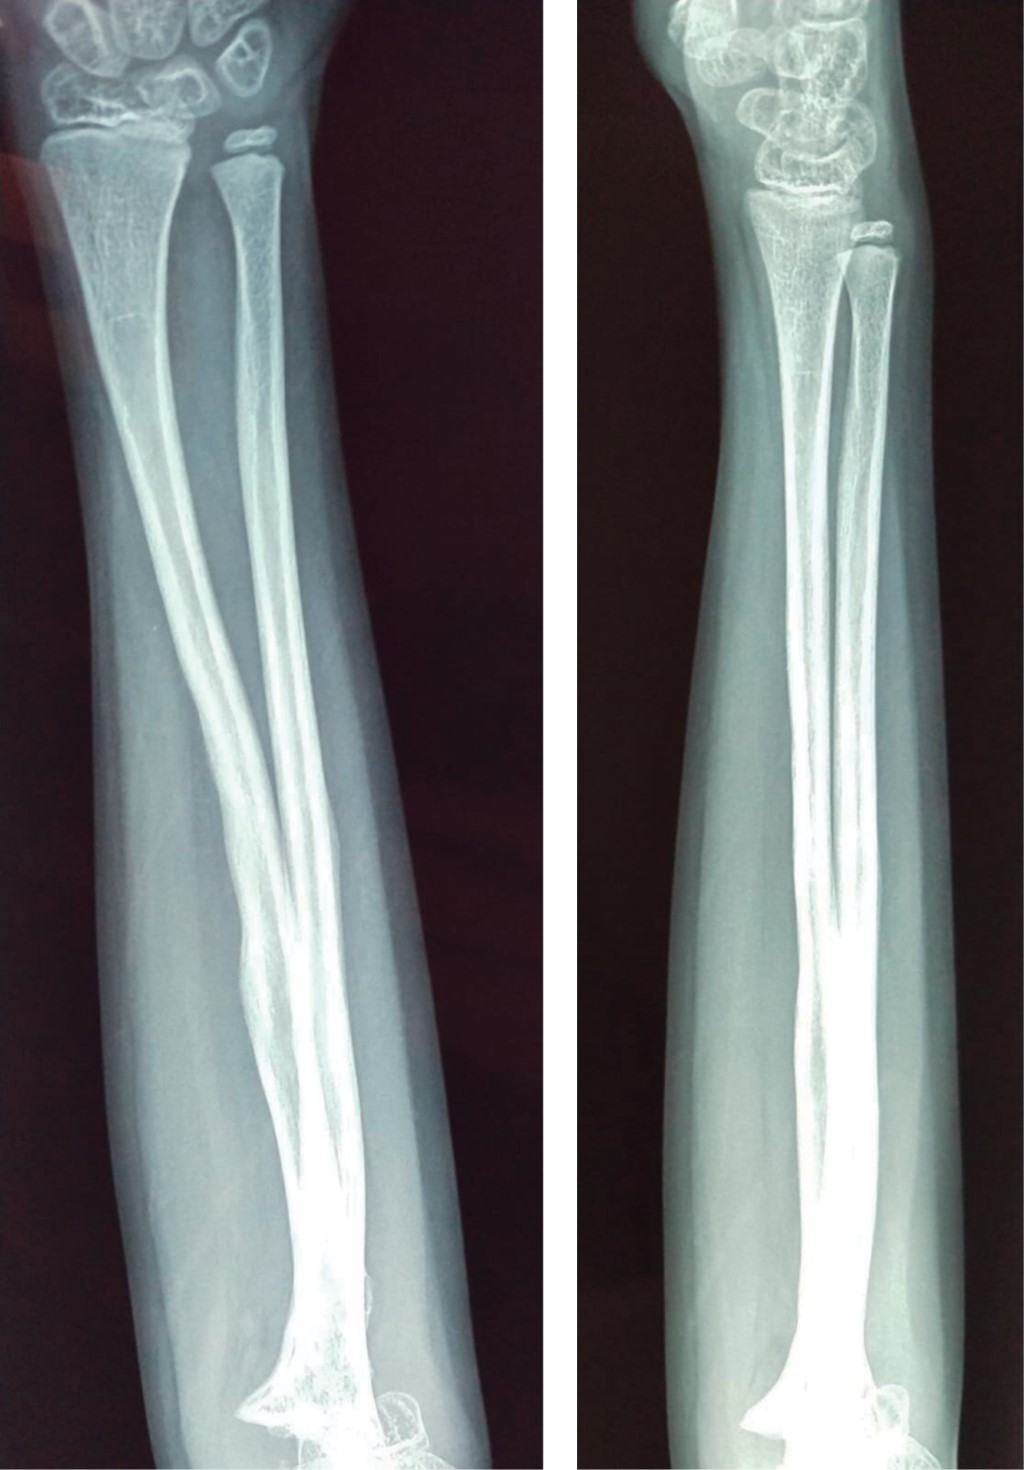

Introduction: the functions of vitamin D are very varied, from the regulation of cell proliferation, the modulation of the immune system, being the intestinal absorption of calcium, phosphorus, and magnesium one of the most important. Low levels of vitamin D are directly related to alterations in bone metabolism. Objective: to present the clinical case of a patient with a forearm fracture and vitamin D insufficiency, showing the complications that can occur in the bone consolidation process, as well as broadening the knowledge of this pathology. Clinical case: the case of a 7-year-old male patient is presented, who suffered a forearm fracture with a low-energy mechanism, evolving with delayed consolidation; there are important alterations of the bone structure after surgical management, when performing the endocrinological study, low levels of vitamin D are found, the bone changes are reversed when adequate levels of vitamin D are achieved. Conclusions: the clinical approach and surgical management in patients with fractures and suspected vitamin D disorders must be meticulous, given the potential complications that we may face.

Figure 1